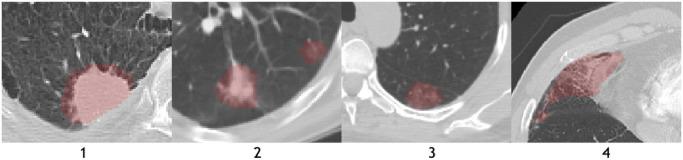

The recent outbreak of Coronavirus Disease 2019 (COVID-19) has led to urgent needs for reliable diagnosis and management of SARS-CoV-2 infection. The current guideline is using RT-PCR for testing. As a complimentary tool with diagnostic imaging, chest Computed Tomography (CT) has been shown to be able to reveal visual patterns characteristic for COVID-19, which has definite value at several stages during the disease course. To facilitate CT analysis, recent efforts have focused on computer-aided characterization and diagnosis with chest CT scan, which has shown promising results. However, domain shift of data across clinical data centers poses a serious challenge when deploying learning-based models. A common way to alleviate this issue is to fine-tune the model locally with the target domains local data and annotations. Unfortunately, the availability and quality of local annotations usually varies due to heterogeneity in equipment and distribution of medical resources across the globe. This impact may be pronounced in the detection of COVID-19, since the relevant patterns vary in size, shape, and texture. In this work, we attempt to find a solution for this challenge via federated and semi-supervised learning. A multi-national database consisting of 1704 scans from three countries is adopted to study the performance gap, when training a model with one dataset and applying it to another. Expert radiologists manually delineated 945 scans for COVID-19 findings. In handling the variability in both the data and annotations, a novel federated semi-supervised learning technique is proposed to fully utilize all available data (with or without annotations). Federated learning avoids the need for sensitive data-sharing, which makes it favorable for institutions and nations with strict regulatory policy on data privacy. Moreover, semi-supervision potentially reduces the annotation burden under a distributed setting. The proposed framework is shown to be effective compared to fully supervised scenarios with conventional data sharing instead of model weight sharing.

最近爆发的 2019 年冠状病毒病(COVID-19)导致对 SARS-CoV-2 感染的可靠诊断和管理的迫切需求。目前的指南是使用 RT-PCR 进行检测。作为诊断影像学的补充工具,胸部计算机断层扫描(CT)已被证明能够揭示 COVID-19 的特征性视觉模式,在疾病过程的几个阶段都具有明确的价值。为了方便 CT 分析,最近的努力集中在使用胸部 CT 扫描进行计算机辅助特征描述和诊断上,这已经显示出了有希望的结果。然而,跨临床数据中心的数据域转移在部署基于学习的模型时带来了严重的挑战。缓解这个问题的一种常见方法是使用目标域的本地数据和注释来对模型进行局部微调。不幸的是,由于全球各地设备的异质性和医疗资源的分布不均,本地注释的可用性和质量通常会有所不同。在 COVID-19 的检测中,这种影响可能更为明显,因为相关模式的大小、形状和纹理都有所不同。在这项工作中,我们试图通过联邦学习和半监督学习来解决这个挑战。采用一个由三个国家的 1704 个扫描组成的多国家数据库来研究在使用一个数据集进行模型训练并将其应用于另一个数据集时的性能差距。专家放射科医生手动对 945 个扫描进行了 COVID-19 发现的标记。在处理数据和注释的变异性时,提出了一种新颖的联邦半监督学习技术,以充分利用所有可用的数据(有或没有注释)。联邦学习避免了对敏感数据共享的需求,这使得它对数据隐私监管政策严格的机构和国家有利。此外,半监督在分布式设置下有可能减少注释负担。与传统的数据共享而不是模型权重共享的完全监督场景相比,所提出的框架被证明是有效的。